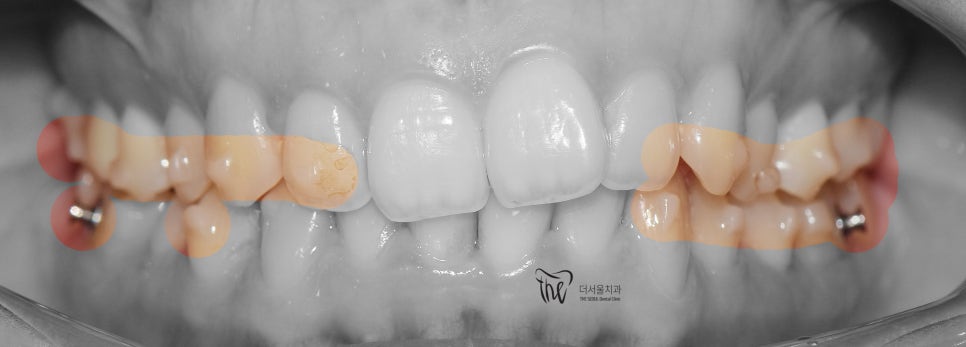

구강 내 사진을 먼저 보여드리면, 윗니가

아랫니를 깊게 물고 있어서 아랫니가 거의

눈에 띄지 않는 것을 보실 수 있습니다.

딱, 전형적 과개교합 의 양상을 보여주고 있습니다.

그러면서 치아의 중심선이 맞지 않으면서

악궁의 크기 또한 비대칭인것을 볼 수 있네요.

올려드린 5개의 중첩사진을 보면,

단순히 압하로 끝날 문제가 아니라는 것을

볼 수 있으면서 클린첵 시뮬레이션에 따라서

치열 및 악궁의 확장에 따른,

그리고 이가 맞물리는 포인트의 위치 변경에

따라서 과개교합 증세가 개선이 되는 것을

한 눈에 볼 수 있습니다.